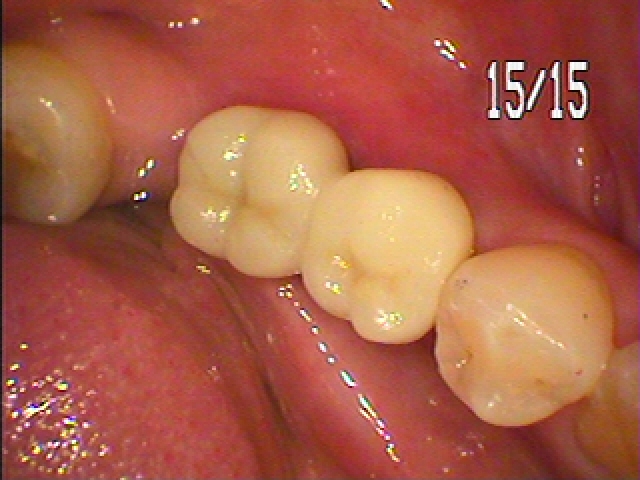

2か月後がこのようになります

型取りを行いオールセラミックにて上部構造を仕上げています

綺麗に仕上がりました